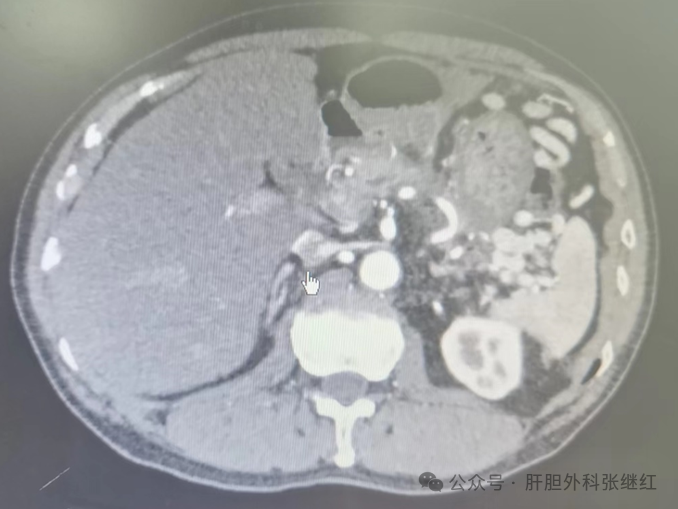

图为张继红团队腹腔镜囊肿胃吻合术前CT、手术照片和术后CT